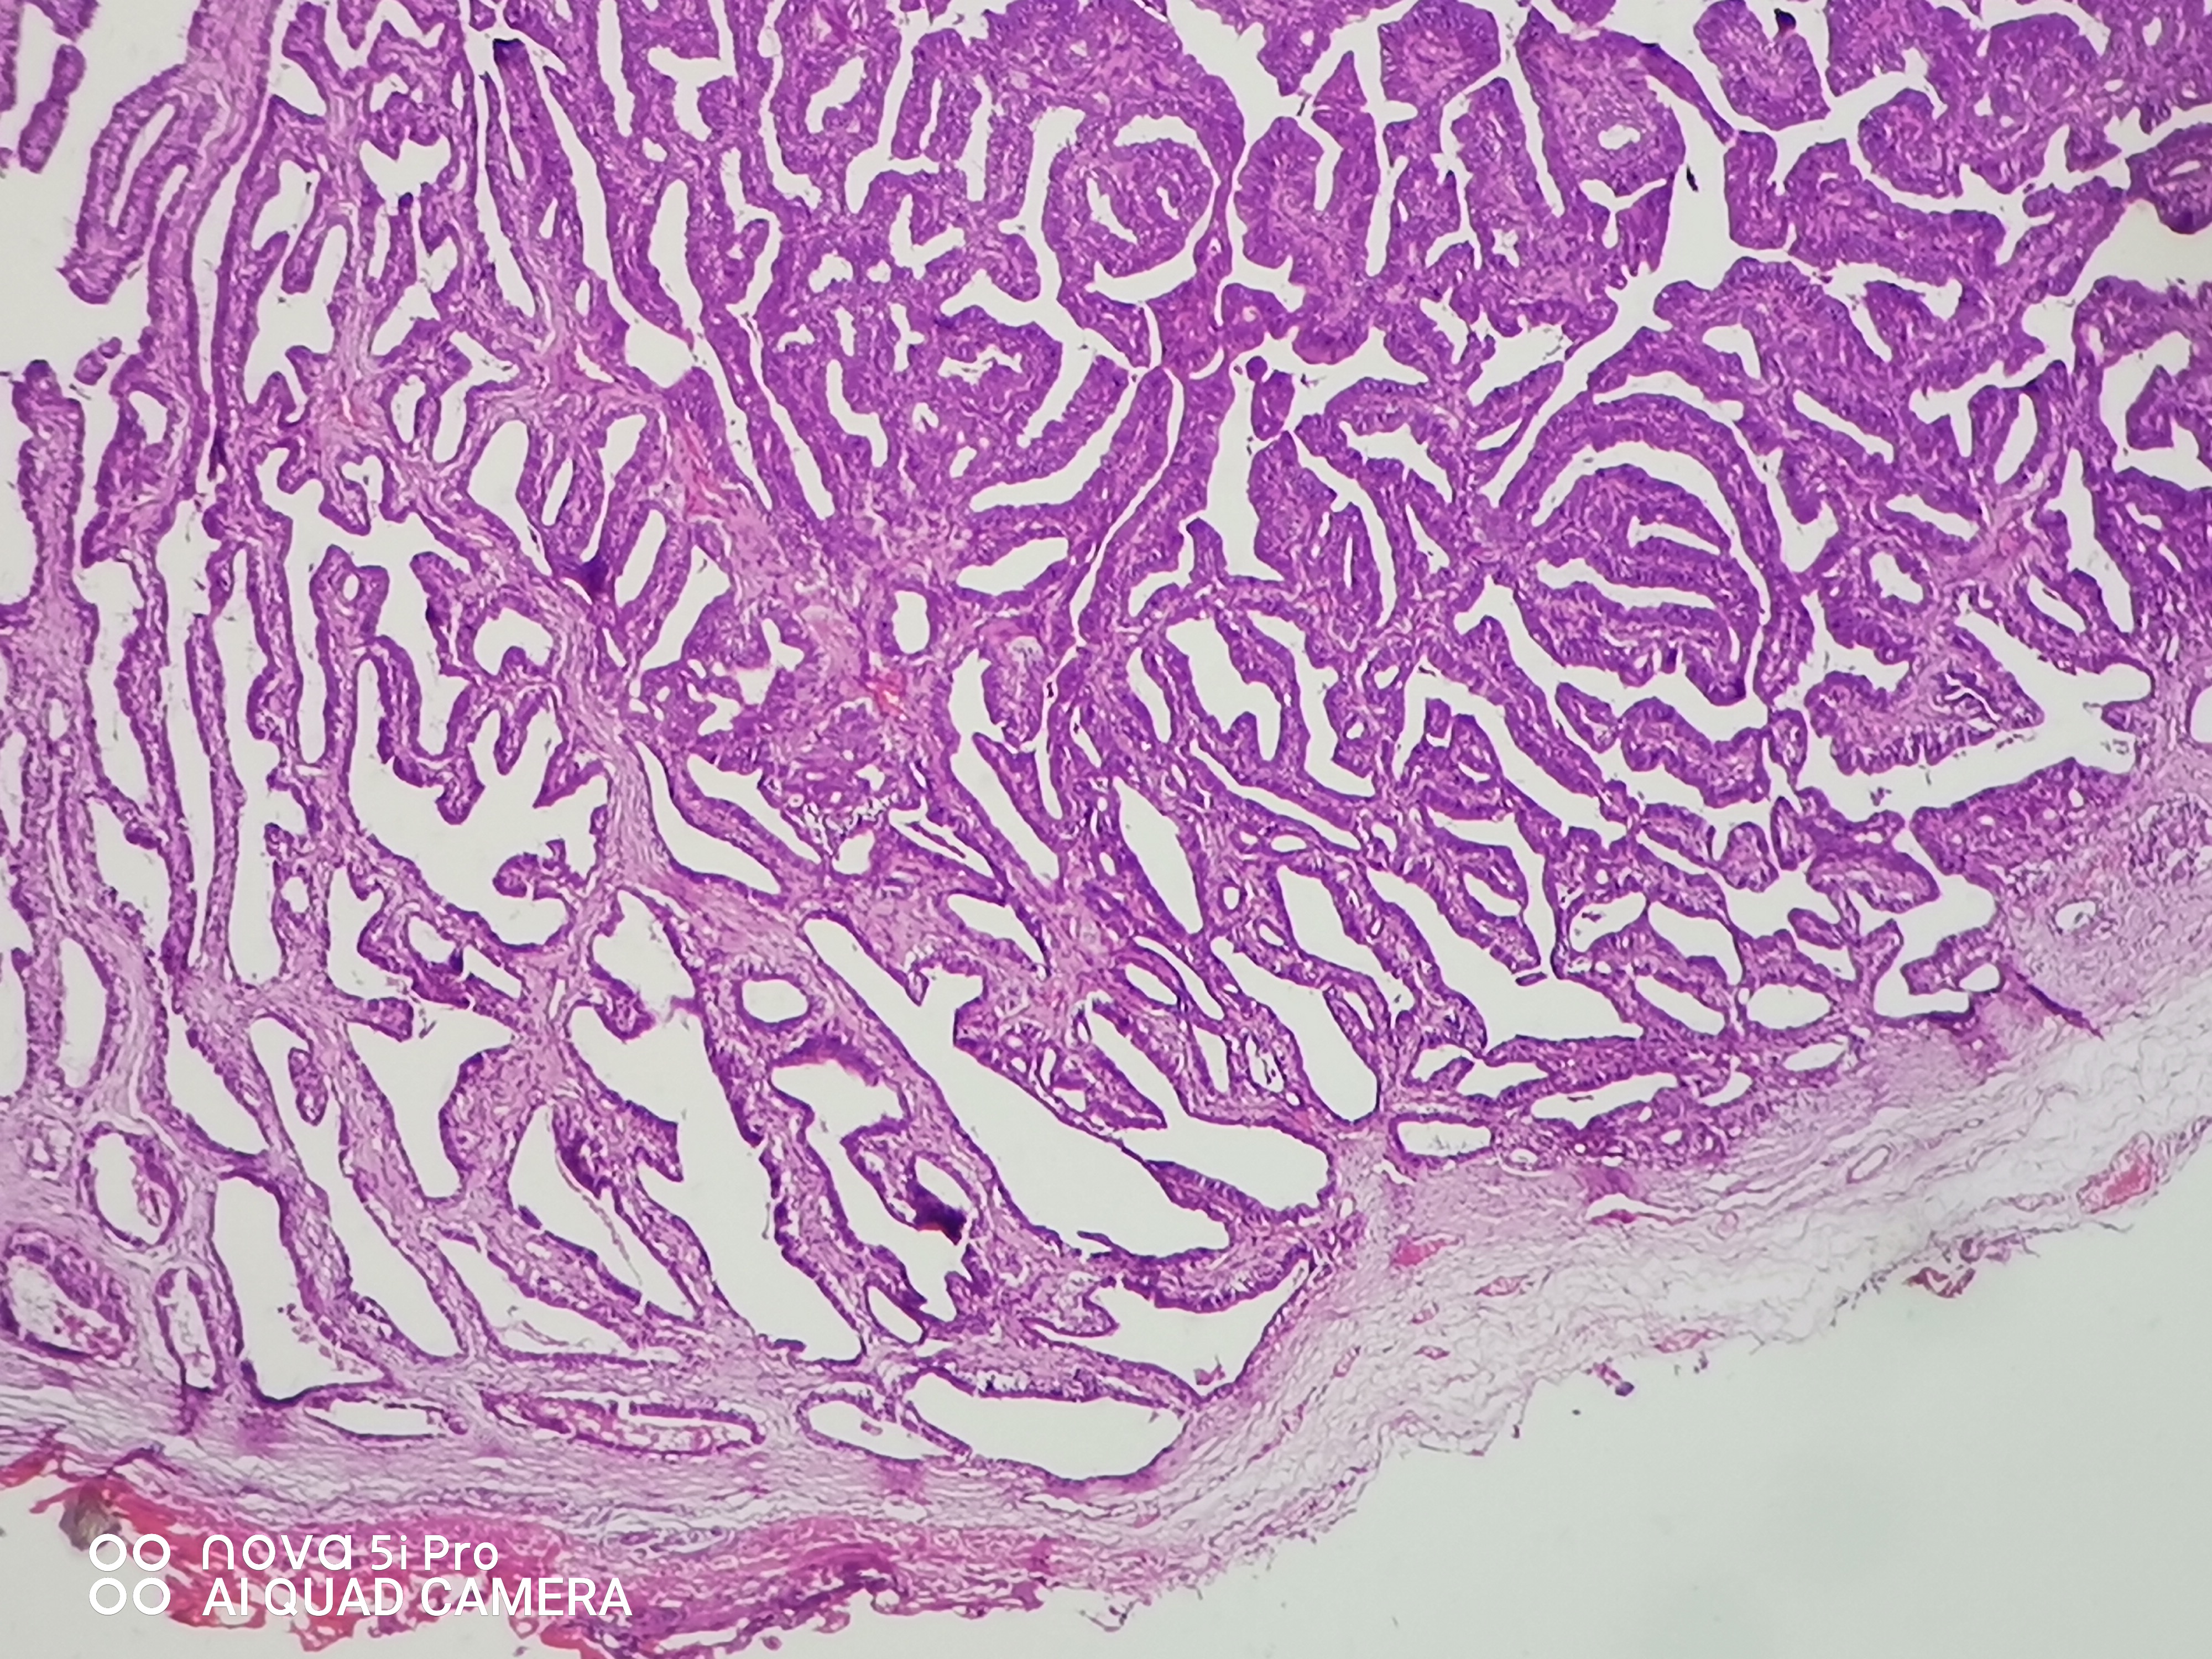

性别年龄41岁临床诊断混合痔,肛门肿块性质待查。

一般病史肛门肿块反复脱出5年,加重2月余。

标本名称肛门肿块

大体所见组织一块,大小约0.7*0.5*0.5cm,对半切开,实性灰白质中,全取。

高级别乳头状肿瘤

考虑:癌变!

乳头状汗腺瘤?

• 云子:  如果是肠上皮的话会有纤毛细胞,会有杯状细胞。杯状细胞的消失对应的是高级别肠上皮细胞病变,然而切片不支持高级别。女性外阴、肛门的这种乳头状生长模式十断头分泌现象,我更首先考虑乳头状汗腺瘤。个人意见,仅供参考!

图1可见断头式分泌,需要鉴别 汗腺肿瘤,标一下CK7.CK20.SATB-2.和P63。

这个病例的医生刚刚打电话联系我了,经省里专家远程会诊也是考虑乳头状汗腺瘤伴轻一中度非典。